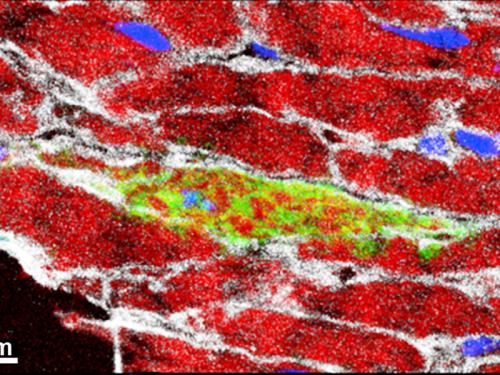

Dado que, en comparación con la gran cantidad de células del músculo cardíaco, las células madre SCA1 representan sólo una pequeña proporción de las células en el músculo del corazón, la búsqueda de ellas es como buscar una aguja en un pajar.

«También se enfrentan al problema de que SCA1 ya no está disponible en las células como una proteína marcadora de células madre después de que han sido transformadas en células de músculo cardíaco. Para probar esto, tuvimos que ser creativos», dice el líder del proyecto Shizuka Uchida. Los investigadores del Instituto Max Planck modificaran genéticamente las células madre hasta el punto de que, además de la SCA1, se produjo otro marcador visible. Incluso si SCA1 estaba posteriormente no es visible, el marcador todavía podría ser detectado de forma permanente.

«De esta manera, hemos sido capaces de establecer que la proporción de las células del músculo del corazón se originan en células células madre SCA1 que aumentan continuamente en ratones sanos. Alrededor de un cinco por ciento de las células musculares del corazón regenera a sí mismas dentro de los 18 meses», dice Uchida. Por otra parte, los ratones que sufren de enfermedades del corazón provocada por el experimento tenían hasta tres veces más de estas células del músculo cardíaco recién formadas.